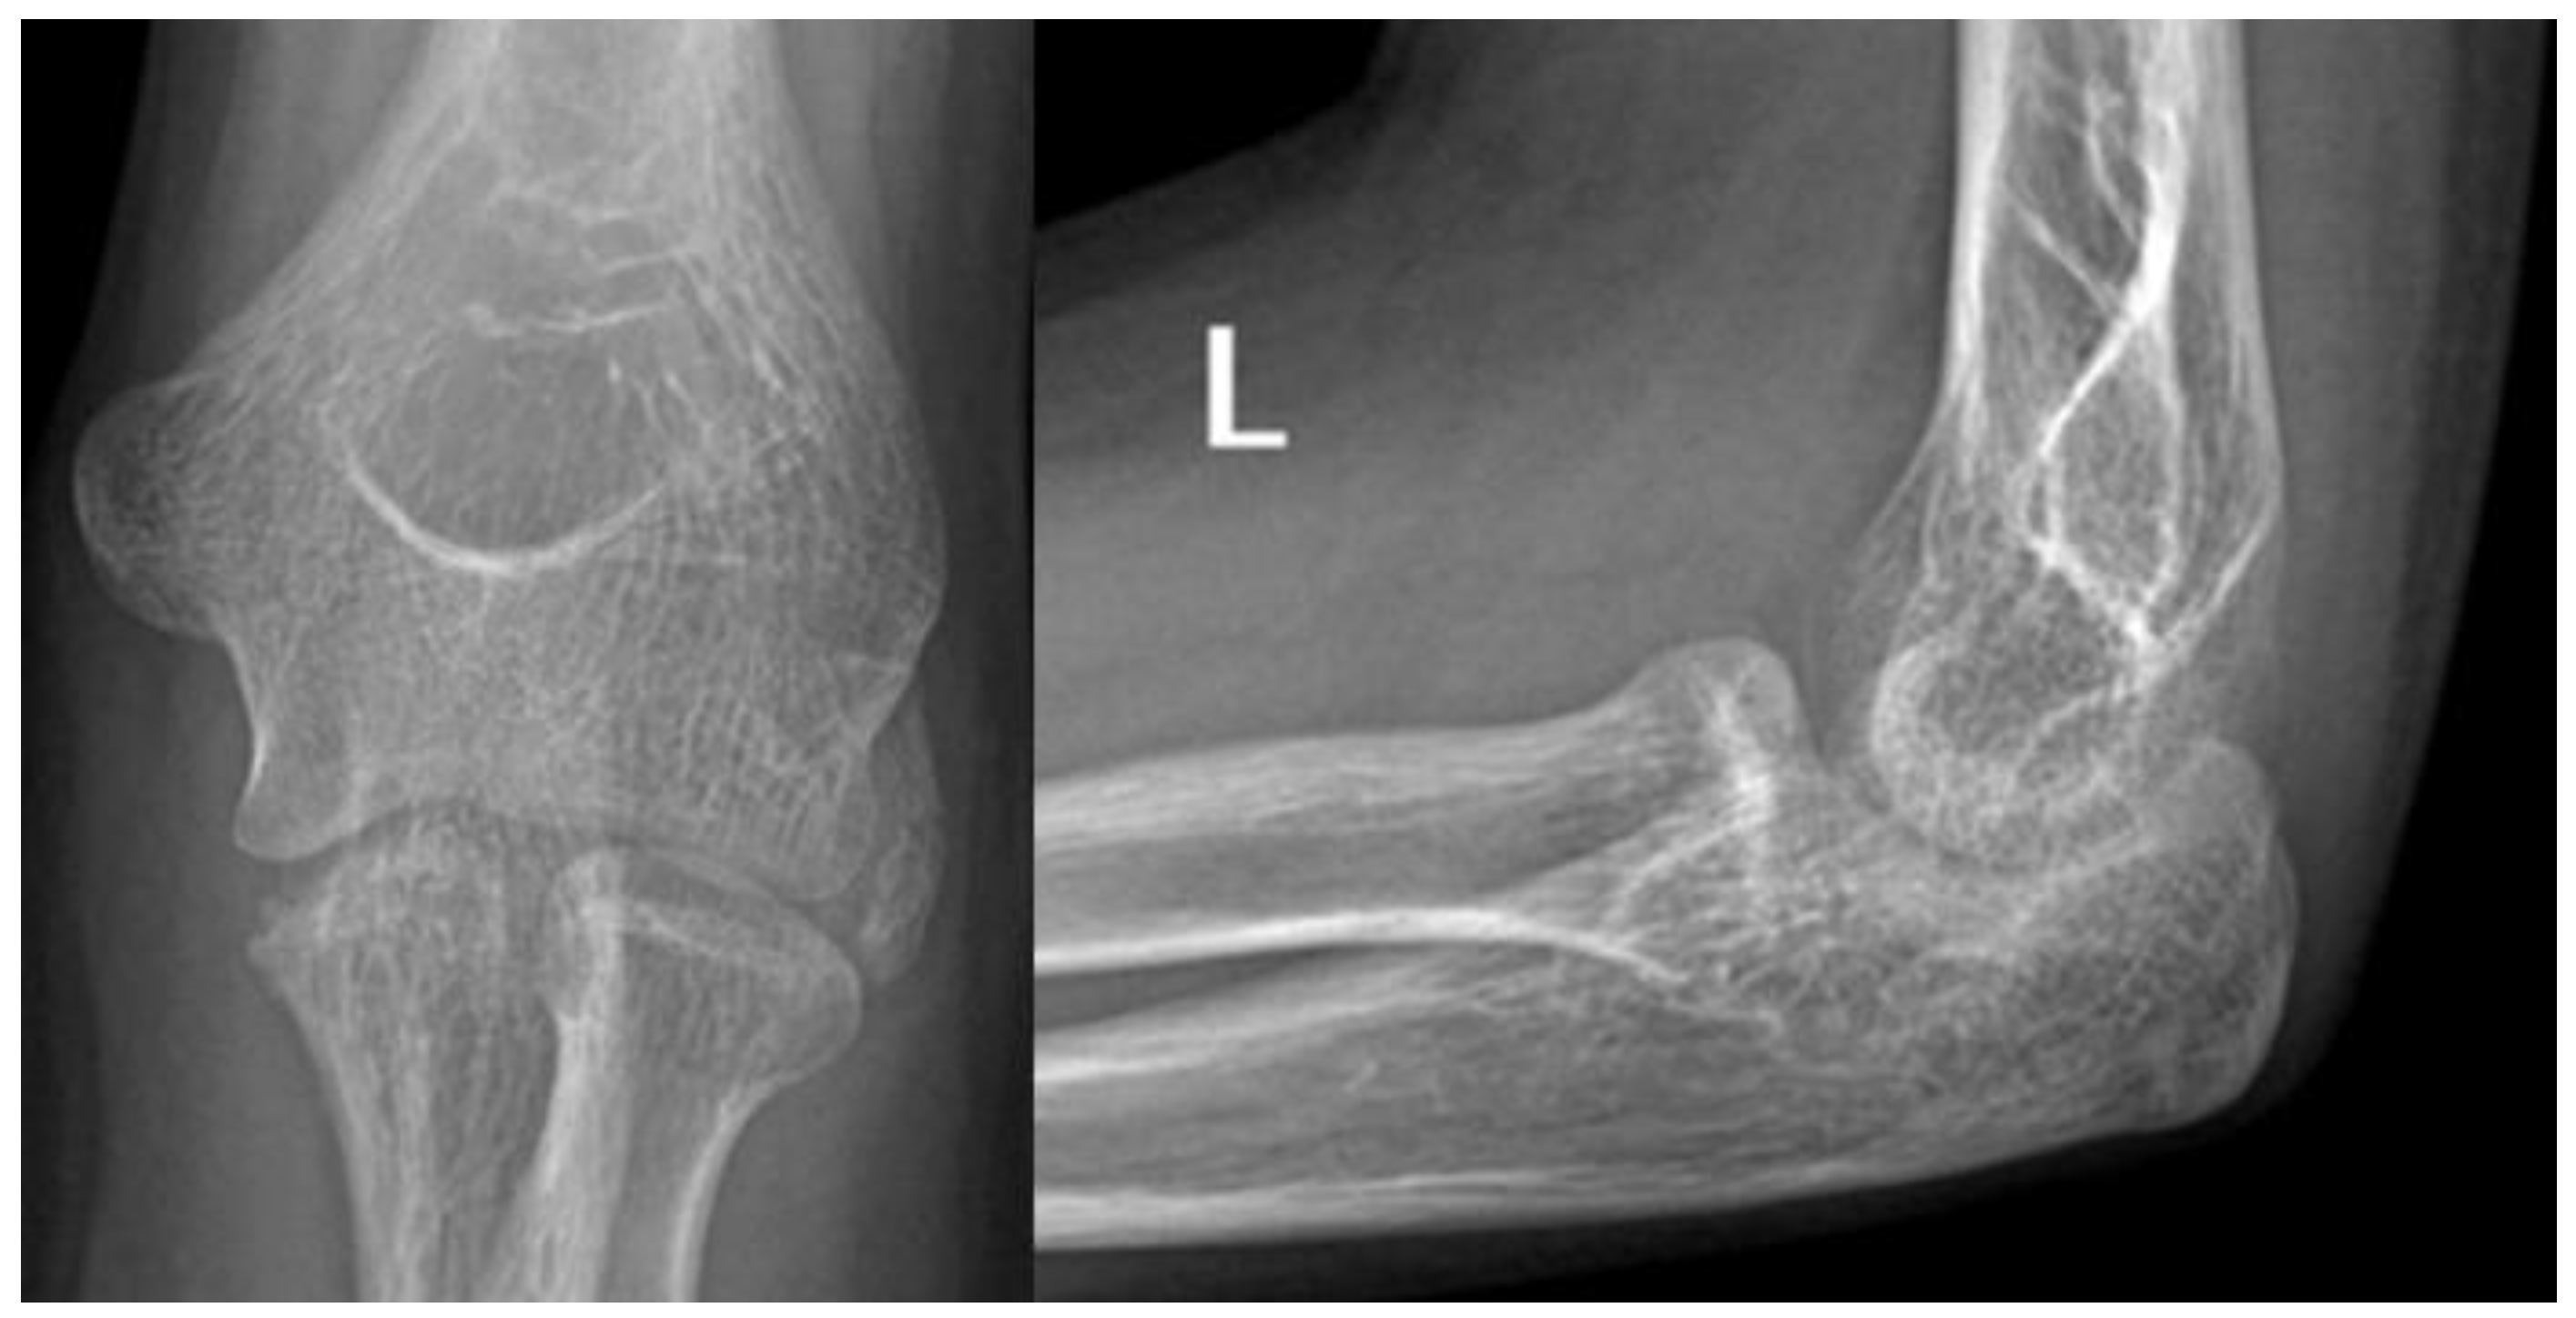

At the age of 13, another injury occurred, and the child complained of a sprain prior to the injury. X-ray imaging showed a posterior elbow dislocation without signs of a fracture (Figure 5). Under anesthesia, the luxation was repositioned. Following repositioning, an image review was performed, and no suspected fracture area was identified. A long upper limb cast was placed for two weeks.

Figure 5. Imaging of the posterior dislocation at age 13, image (A) showing the luxation upon ebow extension and (B) from a lateral view in flexed position.